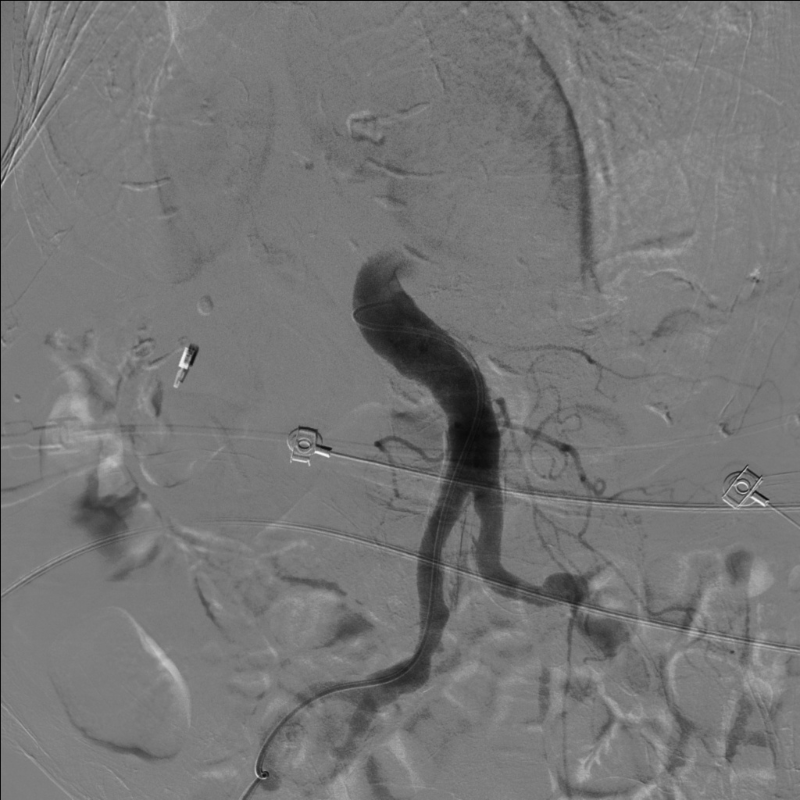

经微导管注入栓塞剂到胃十二指肠动脉全程,造影显示胃十二指肠动脉栓塞彻底,肝内动脉分支血运良好无副栓塞。